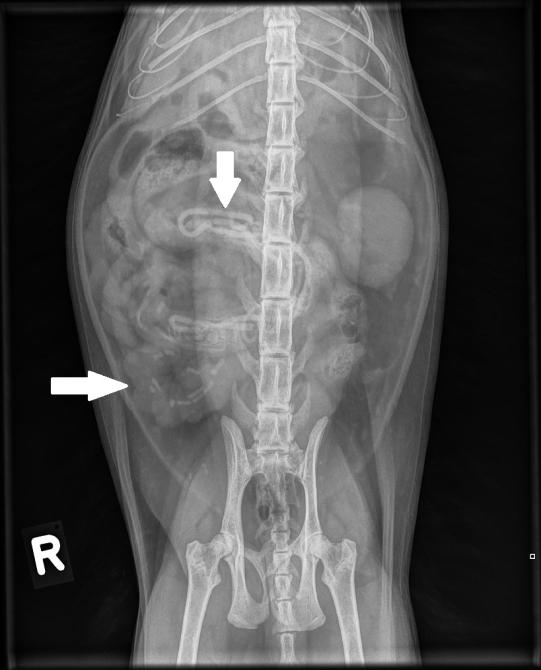

Die Vorgeschichte lässt natürlich aufhorchen, entsprechend werden umgehend Röntgenaufnahmen des Bauches angefertigt. Hier sind diverse längliche, röntgendichte Fremdkörper zu sehen - bei einigen ist unklar, ob sie nicht schon im Dickdarm angelangt und damit problemlos sind; bei anderen besteht insbesondere auf der Aufnahme in Rückenlage der Verdacht, dass sie im Dünndarm stecken und sich dieser über dem Fremdkörper aufgefältelt hat. Das Katerchen muss aufgrund des Darmverschlusses schnellstmöglich operiert werden.